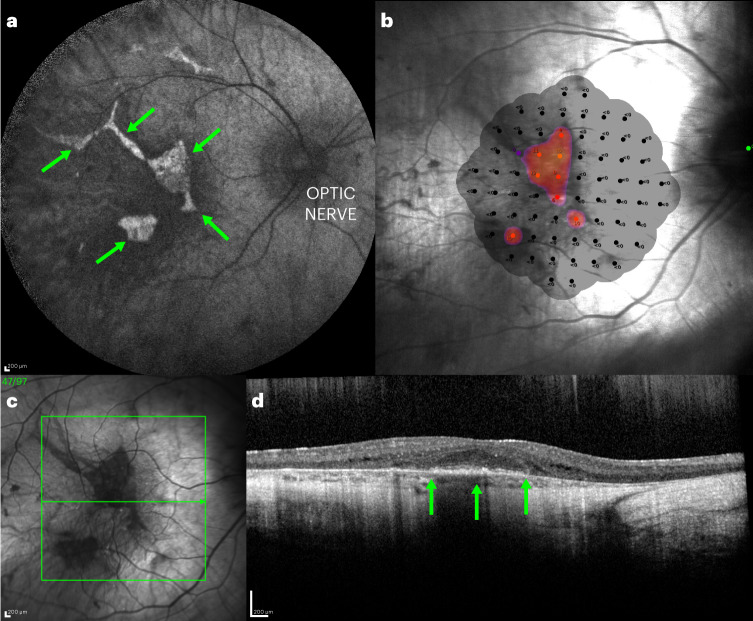

Fig. 1. Retinal images and microperimetry plot from a patient with advanced choroideremia.

a, AF imaging reveals the fluorescent shapes that represent the surviving retinal pigment epithelium centrally (green arrows). b, The microperimetry plot shows that the central triangular area of AF is broadly correlated with the surviving visual field (red dots). c, The green box shows the region of optical coherence tomography scan, with the scan along the green arrow shown in d. d, The surviving outer nuclear layer is the area above the green arrows, with disruption of the outer segments indicating early degeneration.